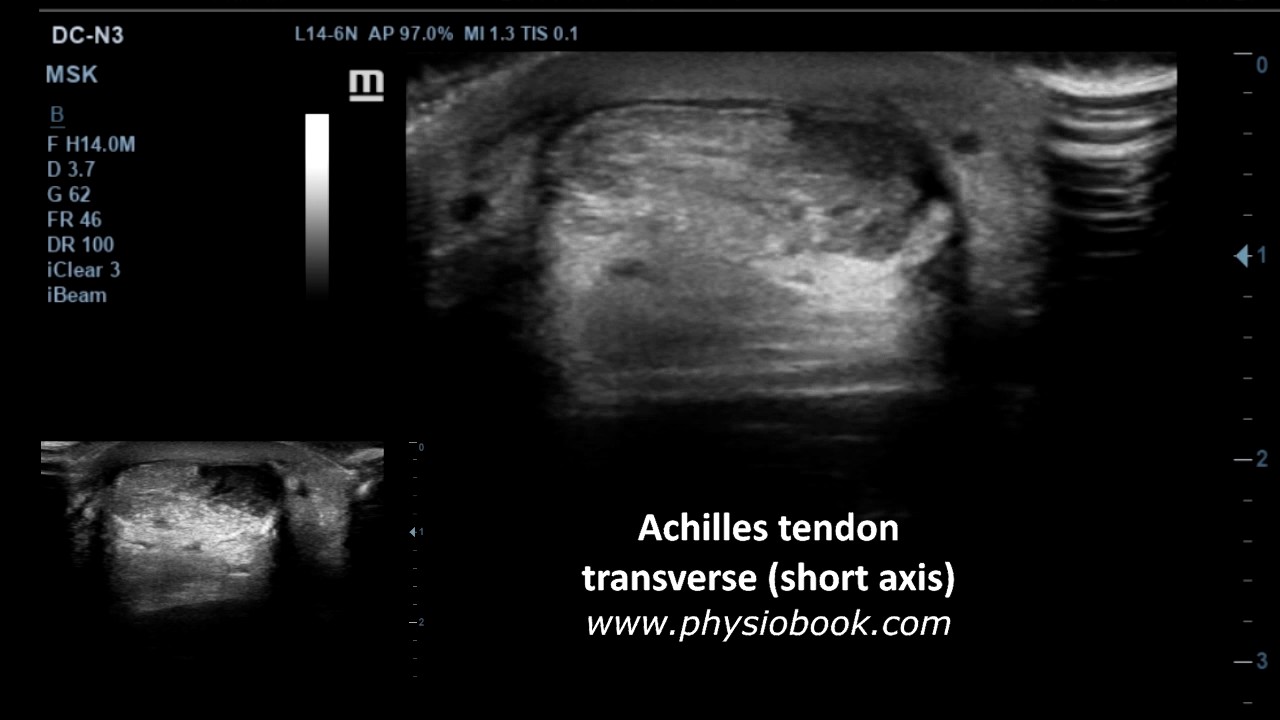

Achilles Tendon Tear - MSK Ultrasound - YouTube

Achilles tendon tear - MSK ultrasound - YouTube www.youtube.com

ultrasound achilles tendon tear msk